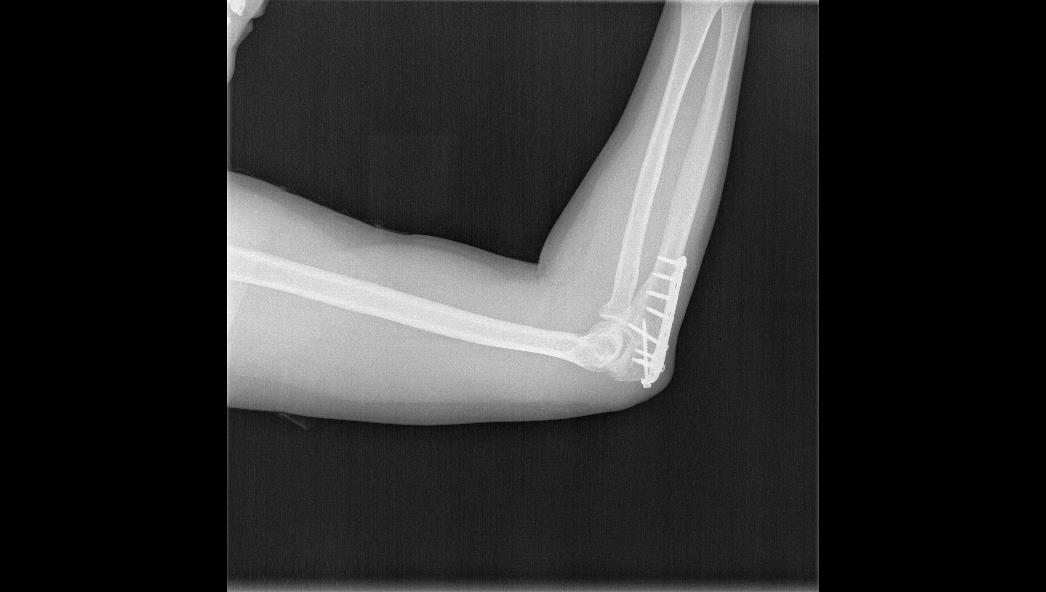

Low plate-and-screw profile and rounded plate edges minimize potential for tendon and soft tissue irritation.

TRUE LOCK Olecranon Anatomic Plates are precontoured for anatomic fit. No need to bend during teh surgery.

Long proximal extension and multiple screw options to secure small olecranon fragments to help neutralize the forces of the triceps muscle.